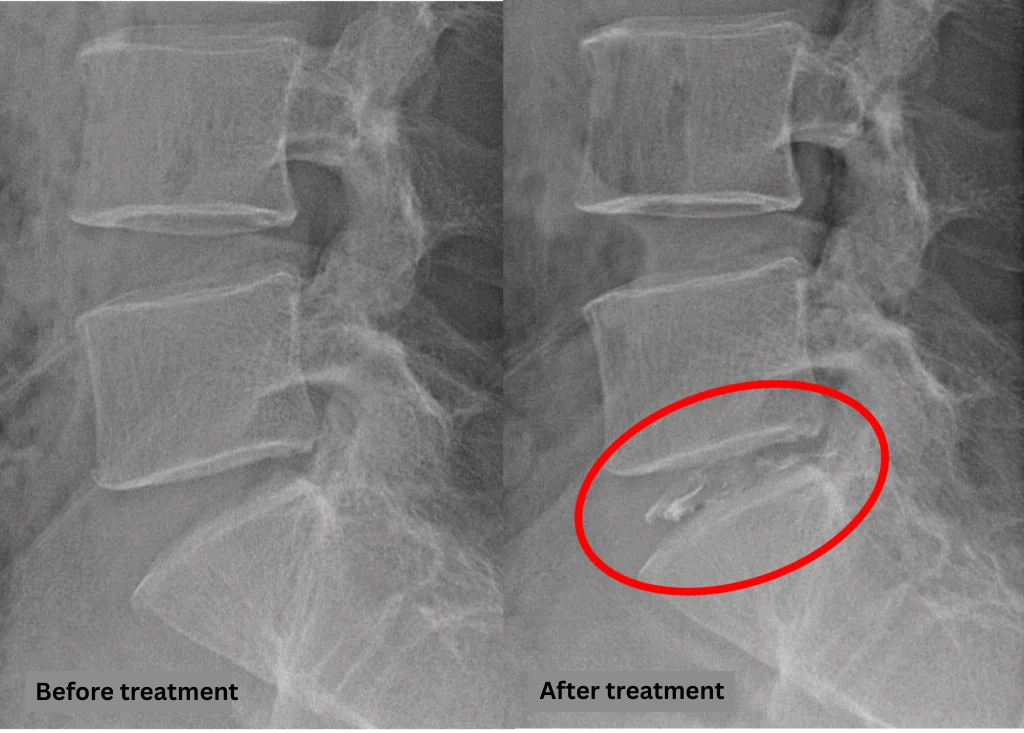

- L5/S: Disc degeneration, disc herniation

The above findings were also observed on the imaging.

These imaging findings suggest that compression of the spinal canal at the L5/S level is the most likely cause of the patient’s symptoms.

After consulting with the patient, the Cellgel Method was performed on L5/s.